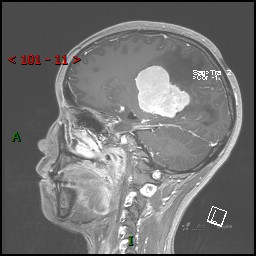

视物模糊发现颅内占位,“豆蔻年华”却承受开颅之痛,所幸一切顺利---结果公布~

患者年龄:14岁

简要病史:患者于1月前无明显诱因出现视物模糊,无明显头痛头晕,无恶心呕吐,无昏迷,无肢体偏瘫等症状,就诊于当地医院头部CT考虑:右侧丘脑、脑室占位。予以对症处置后家属为求进一步诊治来我科,以“颅内占位”收入院。 起病以来,精神、饮食、睡眠欠佳,大小便正常,体力下降,体重无明显变化。

临床诊断:脑室占位

MRI平扫